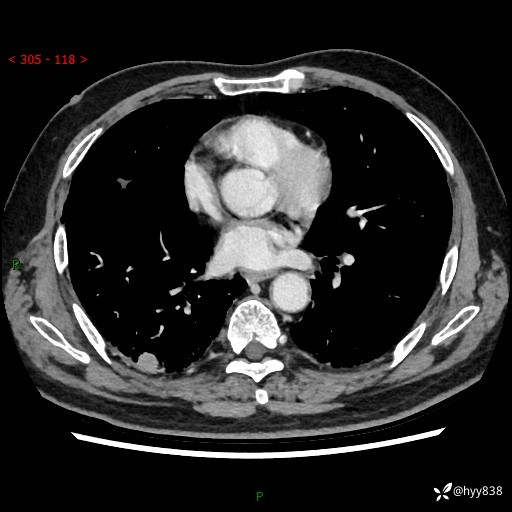

71岁/男,咳嗽伴气促半月。一年前肺手术史,又见两个结节,穿刺结果意外---结果公布~

【现病史】:患者半月前无明显诱因出现咳嗽、咳痰,为白色粘痰,无明显加重与缓解因素,伴气促,无发热,无大量脓痰,无胸痛、咯血,无哮鸣音,到我院就诊,胸部CT示右肺结节增大,并口服药物治疗无明显好转,具体用药不详,为求进一步治疗随来我院,经门诊以“孤立性肺结节”收入我科。 病程中患者精神、饮食可,睡眠不佳,大小便正常,体力下降,体重未见明显下降。

[既往史]:2022-06于当地第一人民医院确诊慢阻肺,现规律使用杰润(1次/日);2023-04-06于当地市第一人民医院行胸腔镜右肺上叶楔形切除术+右肺上叶切除术+淋巴结清扫术+胸膜黏连松解术,确诊为右肺鳞癌 pT2aN0M0 Ib期

【检查】:胸部CT平扫+增强